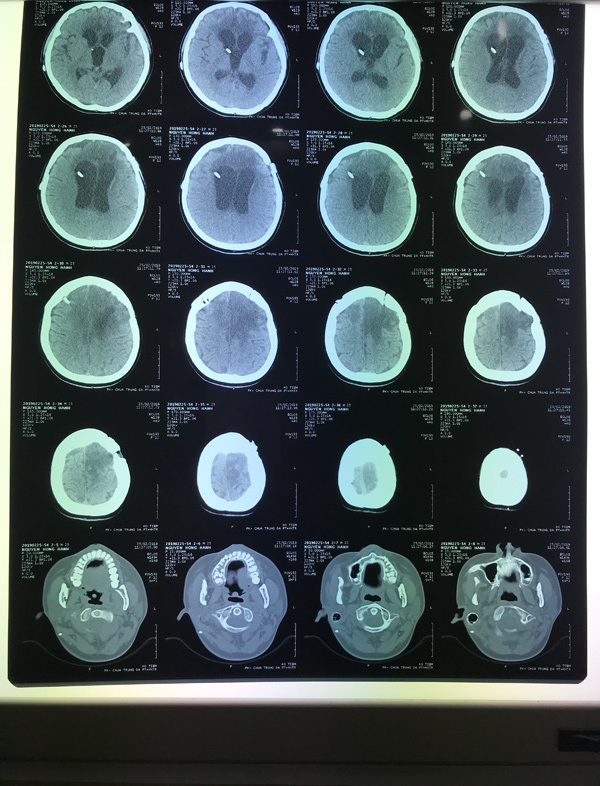

Hình ảnh khối u di căn trong não

Tại BV K, bác sĩ kết luận, H. bị xuất huyết não, từng được cắt u não vi phẫu, dẫn lưu não thất nhưng hiện tại H. đã bị di căn sang ung thư buồng trứng rồi di căn não.